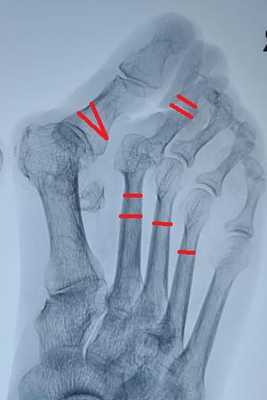

Молоткообразная деформация 3-4 пальцев устраняется за счёт уменьшения нагрузки на головки 3-4 плюсневых костей (остеотомии вейль, хелал, ДММО) я выбрал ДММО как самую быструю, простую и эффективную.

Нормальная парабола головок плюсневых костей восстановлена в обеих плоскостях. Определяется консолидация 2-3-4 плюсневых костей несмотря на отсутствие фиксации. Первая плюсневая кость находится в не оптимальной позиции.

Пациентка А. 57 лет. Тяжёлое поперечное плоскостопие. Молоткообразная деформация 2-3 пальцев. Деформация Тейлора.

Определяется выраженное поперечное распластывание стопы, искривление всех 5 пальцев стопы, выраженная боль под головками 2-3-4 плюсневых костей.

остеотомия скарф 1 плюсневой кости

остеотомия акин основной фаланги 1 пальца

остеотомия вильсон 5 плюсневой кости

остеотомия вейль без фиксации 2-3-4 плюсневых костей

артропластическая резекция проксимальных межфаланговых суставов 2-3 пальцев с фиксацией спицами